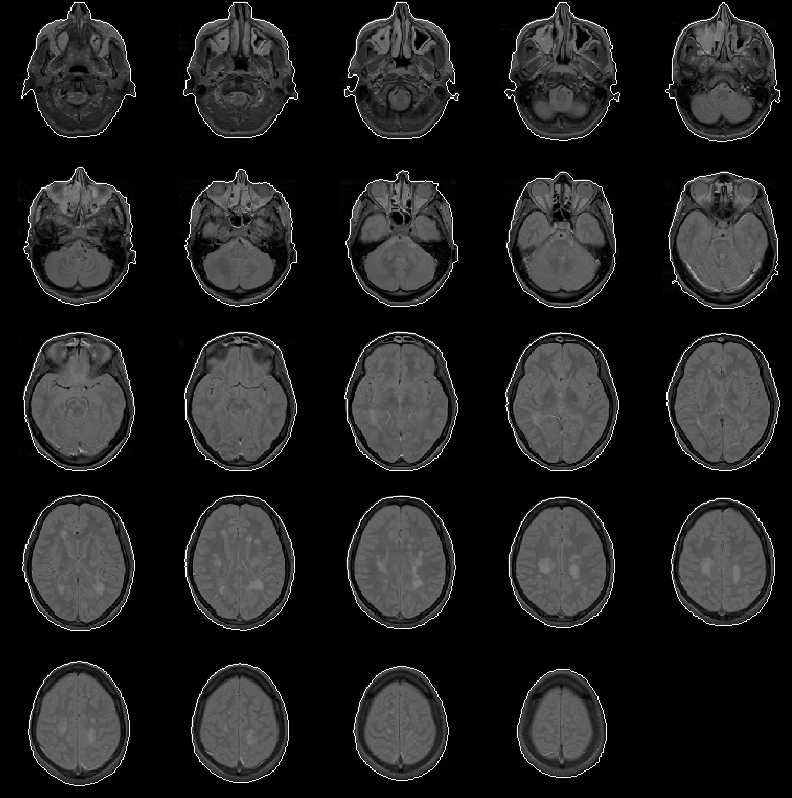

Figure 8.8 shows that the head mask produced for Data Set 3 is comparable to those produced for Data Sets 1 and 2. Here, the head mask is relatively error-free.

Figure 8.8: The head mask for MRI Data Set 3 overlaid on the PD-weighted scan.